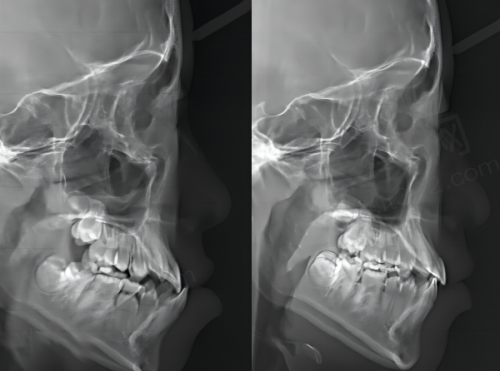

医院设有数字化种植中 心、数字化正畸中 心等,这些数字化技术的应用大大提高了治疗的精细度和效率。在数字化种植中,医生可以通过口腔CT等设备获取患者口腔的三维数据,然后在电脑上进行模拟种植,提前规划好种植体的位置、角度和深度,这样在实际种植过程中就能更加精细,减少手术创伤,缩短修复时间。在数字化正畸方面,医生可以利用数字化模型分析患者牙齿的排列情况,制定个性化的矫正方案,还能让患者提前看到矫正后的成效。

西安中诺口腔医院的种植牙技术备受赞誉,尤其是立得用种植牙。这种技术具有即种即食的特点,患者在种植牙齿后短时间内就可以正常饮食。它的原理是通过特殊的种植技术和种植体设计,让种植体能够更快地与牙槽骨结合,实现稳定的支撑。特别多种过牙的顾客都反映成效不错,大大改善了他们的口腔功能和生活质量。